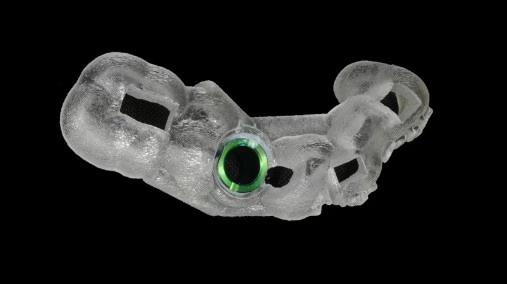

Máng hướng dẫn phẫu thuật cá nhân hóa: dụng cụ được làm riêng cho từng bệnh nhân để hỗ trợ bác sĩ đặt trụ Implant đúng vị trí. Khi phẫu thuật, bác sĩ chỉ cần khoan qua các lỗ định hướng trên máng

Máng hướng dẫn phẫu thuật cá nhân hóa